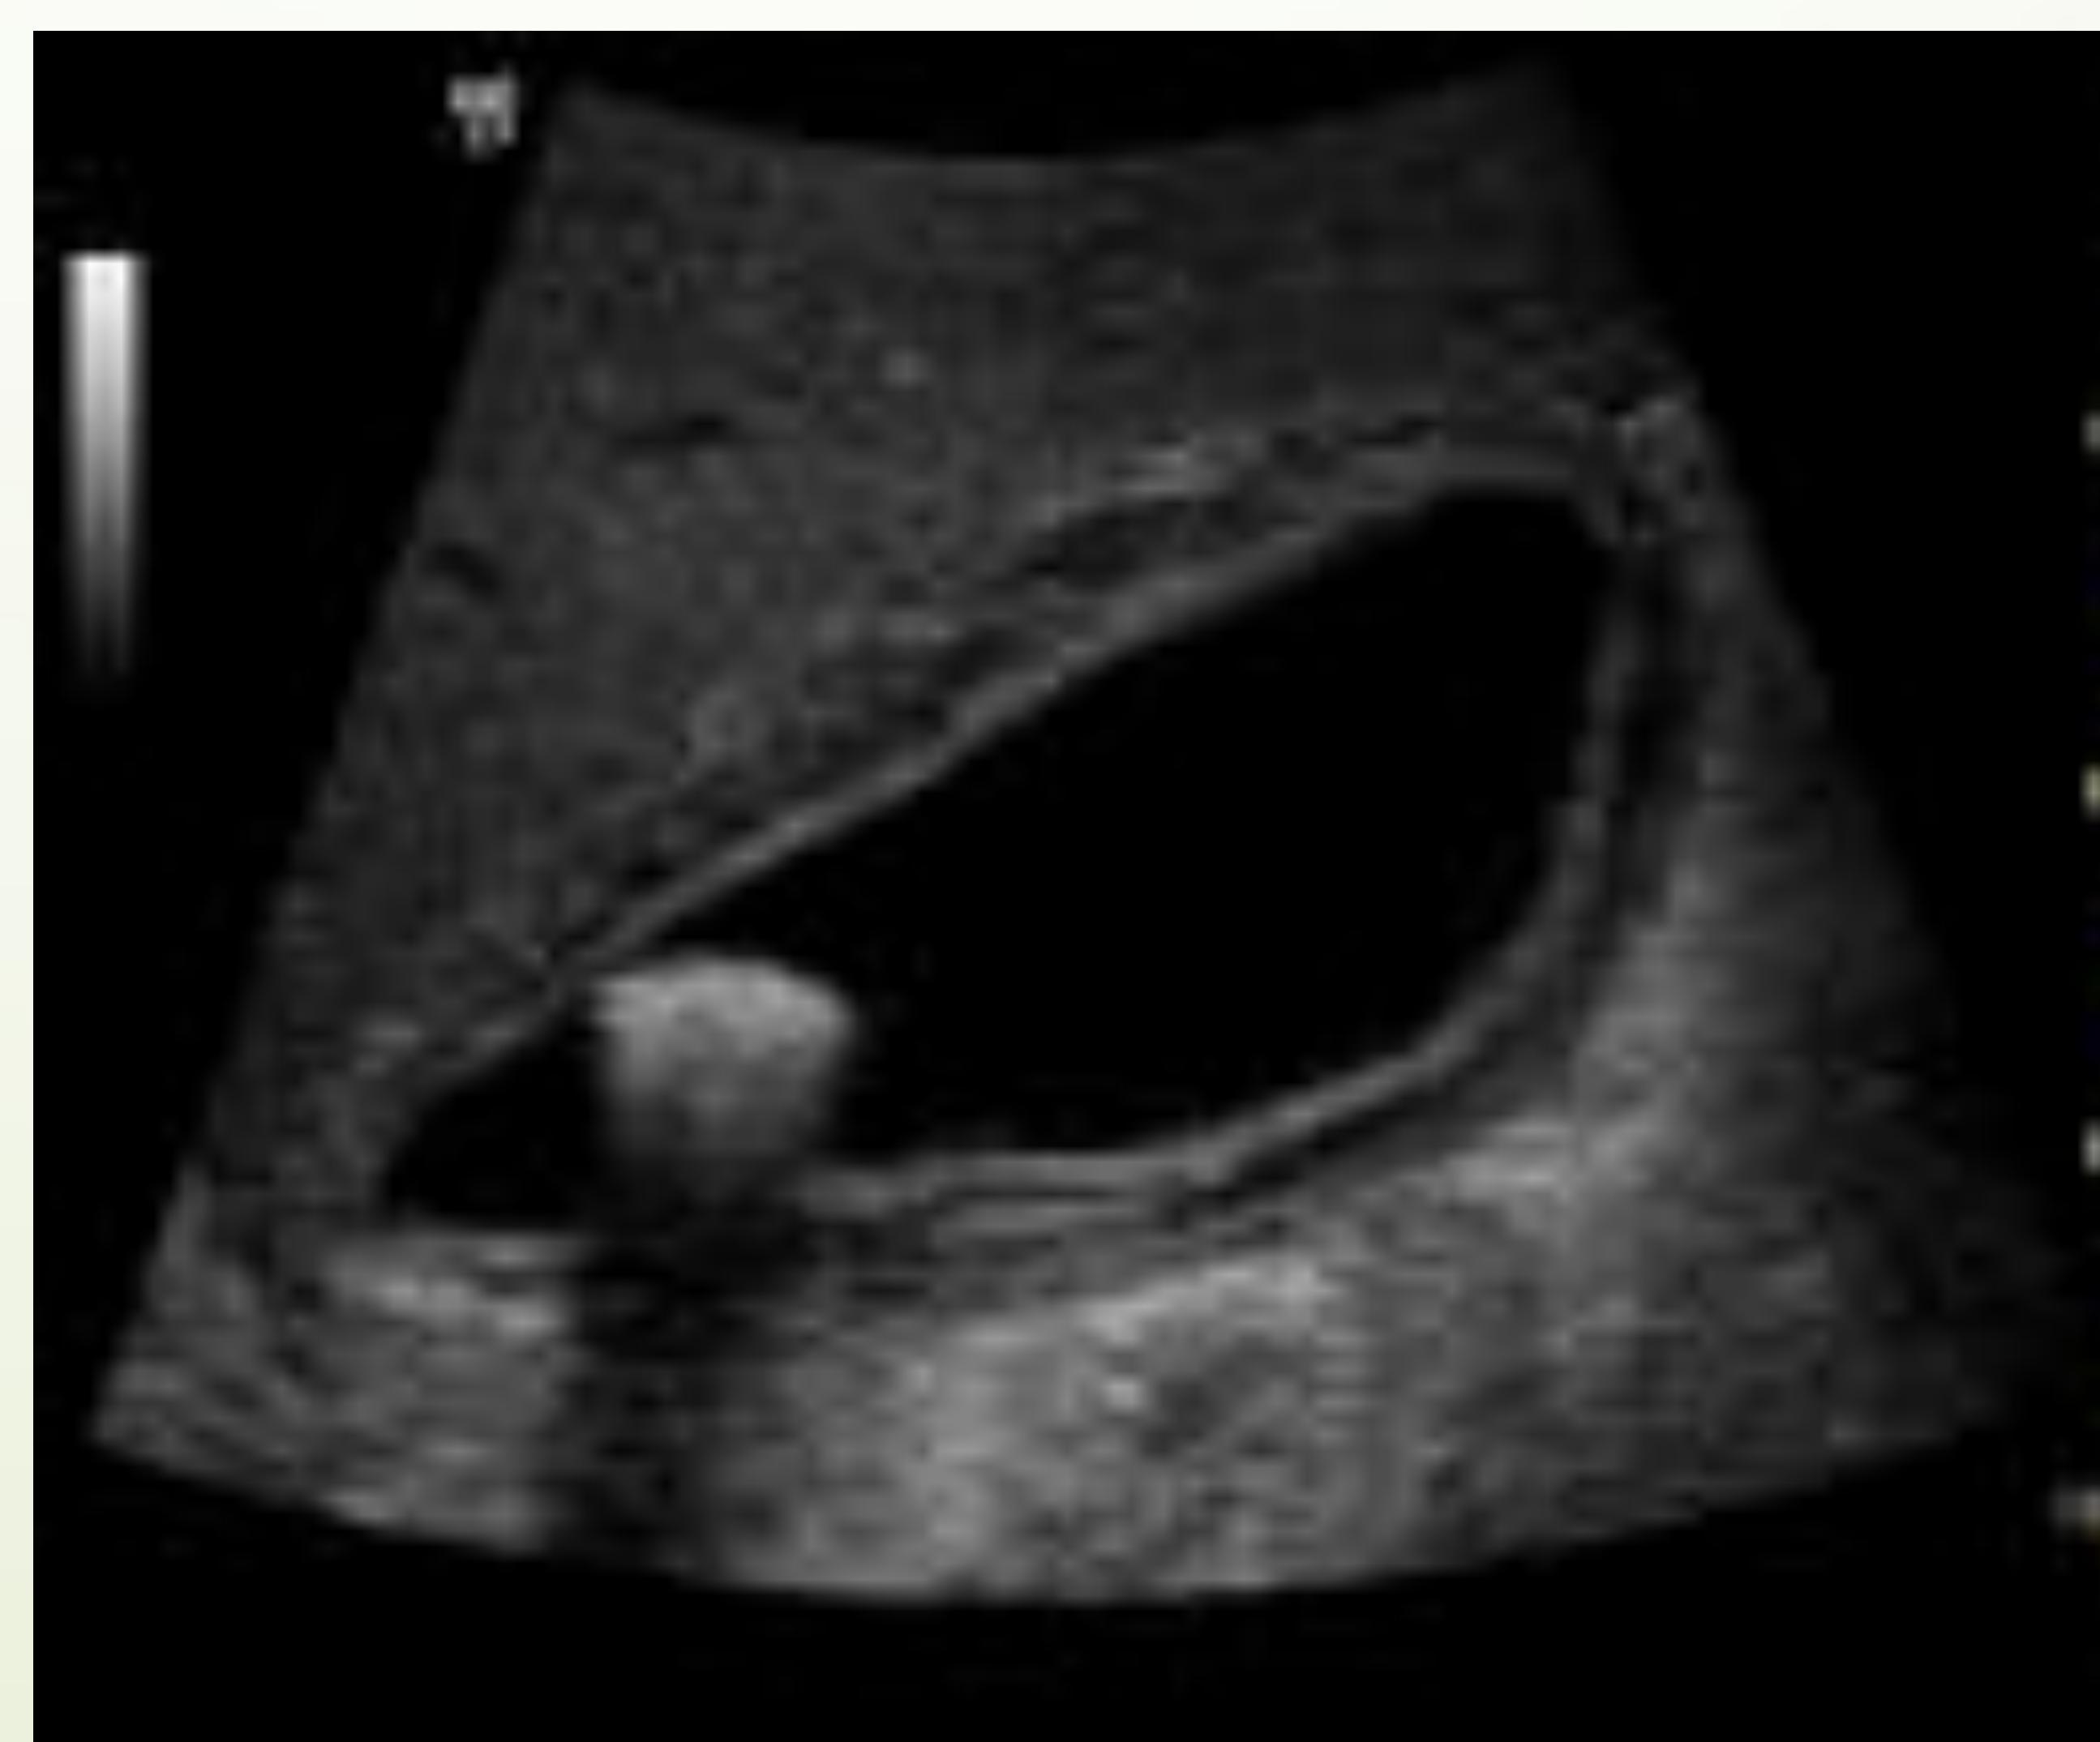

Case #4: Small Bowel Obstruction (SBO)

Upright abdominal X-ray showing multiple air-fluid levels.

POCUS: Dilated bowel > 2.5cm with to-and-fro peristalsis.

Ultrasound B-mode scan. Case #4

- 35‑year‑old healthy female presents to the ED with nausea, vomiting (since yesterday) and generalized abdominal pain. No fever or chills; anorexia present. Last bowel movement ≈ 2 days ago.

- Medical history: none.

- Surgical history: status post hysterectomy for fibroids (adhesive risk).

- Point‑of‑care ultrasound (POCUS) can aid early detection:

- Dilated loops > 2.5 cm

- “Tanga” sign (hyperactive to‑fro peristalsis)

- Wall thickening, reduced peristalsis